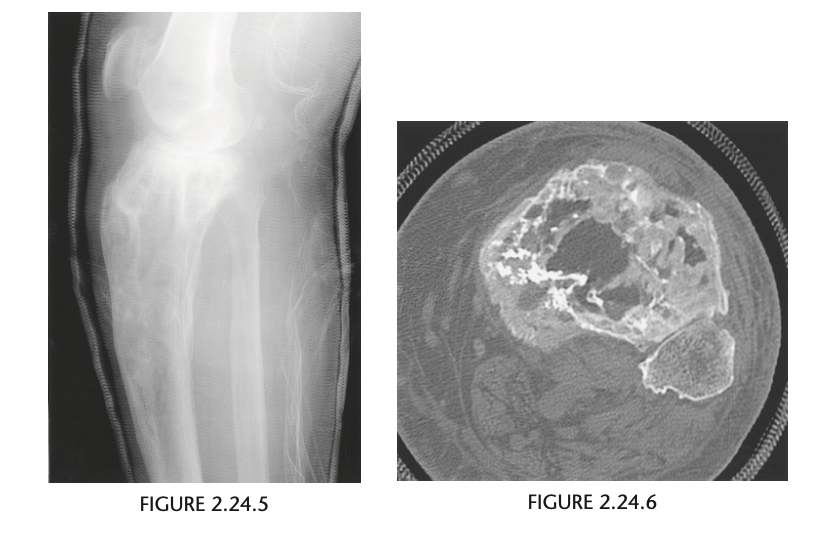

An anteroposterior view of the pelvis

(Fig. 2.24.1) in an elderly man shows extensive thick-

ening of the right iliopectineal line (arrows) with

coarsening of the trabecular pattern and increased

sclerosis throughout the entire right hemipelvis.

In the long bones of the lower extremity, corti-

cal thickening, increased trabecular coarseness, and

bowing can be seen (Fig. 2.24.5), and CT can confirm

these findings (Fig. 2.24.6).